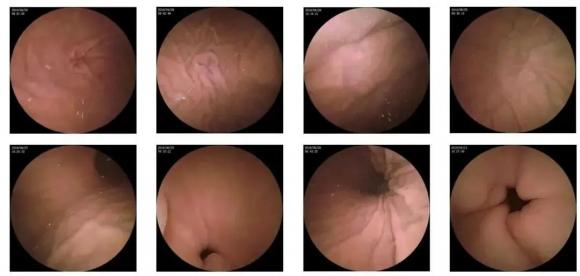

二、高清圖像,精確診斷

膠囊機(jī)器人的專利三鏡片鏡頭,可深入觀察0.04毫米微小單位,每秒可拍高達(dá)4張高清醫(yī)學(xué)照片。

醫(yī)生通過(guò)智能閱片系統(tǒng),可自動(dòng)對(duì)海量圖像識(shí)別過(guò)濾,智能篩選,能有效提升醫(yī)生檢查及閱片效率。

任何細(xì)微的胃部病變,如胃潰瘍、胃出血、息肉等都無(wú)所遁形,盡在大圣磁控膠囊式內(nèi)窺鏡系統(tǒng)的掌握之中。